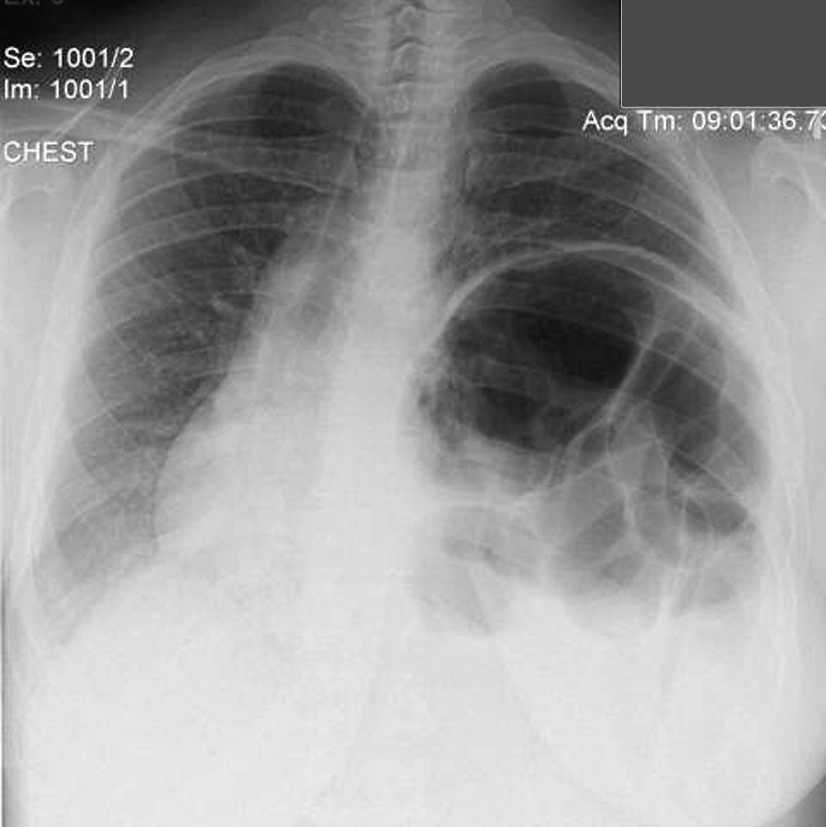

Place one hand on your abdomen and breathe deeply. Reduced number of alveoli air sacs required for normal breathing. In severe cases when there is no simple treatment that can relieve dyspnea your doctor may prescribe morphine. Congenital diaphragmatic hernia CDH. There is usually a long history of heavy smoking. Shortness of breath may be accompanied by wheezing. Diaphragmatic dysfunction caused by transverse myelitis or leukemic infiltration of the cervical spinal cord in a patient with leukemia and shortness of breath. To treat phrenic nerve irritation This condition can be managed with a breathing pacemaker which takes over the responsibility of sending messages to the diaphragm. The cause for shortness of breath was thought primarily due to stable angina on tread mill test positive finding but Chilaiditis syndrome should also be considered as a cause for the shortness of breath.

The rise in intraabdominal pressure further increases intrathoracic and lung volume by pushing the lower rib cage outward. In severe cases when there is no simple treatment that can relieve dyspnea your doctor may prescribe morphine. Diaphragmatic dysfunction caused by transverse myelitis or leukemic infiltration of the cervical spinal cord in a patient with leukemia and shortness of breath. Diaphragmatic plication a surgical procedure that pulls the diaphragm down by introducing a repeated series of continuous sutures across the diaphragm and pulling the muscle taut. A bedside fan or open window with a breeze are also simple but very effective treatments to lessen dyspnea. Depending on the severity of injury to the diaphragm some doctors recommend non-surgical options to treat the breathing issues associated with diaphragm weakness and paralysis. P E Pulmonary embolism.